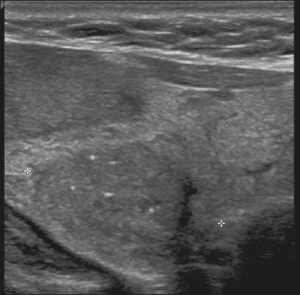

Hình 21. Hình ảnh nhân giáp dạng đặc (2 điểm), giảm âm (2 điểm), cao hơn rộng (3 điểm), có đường bờ không xác định (0 điểm), và không có các ổ tăng âm hay bóng lưng (0 điểm). Do đó, tổng điểm là 7 điểm và mức độ nguy cơ được phân loại là TR5.